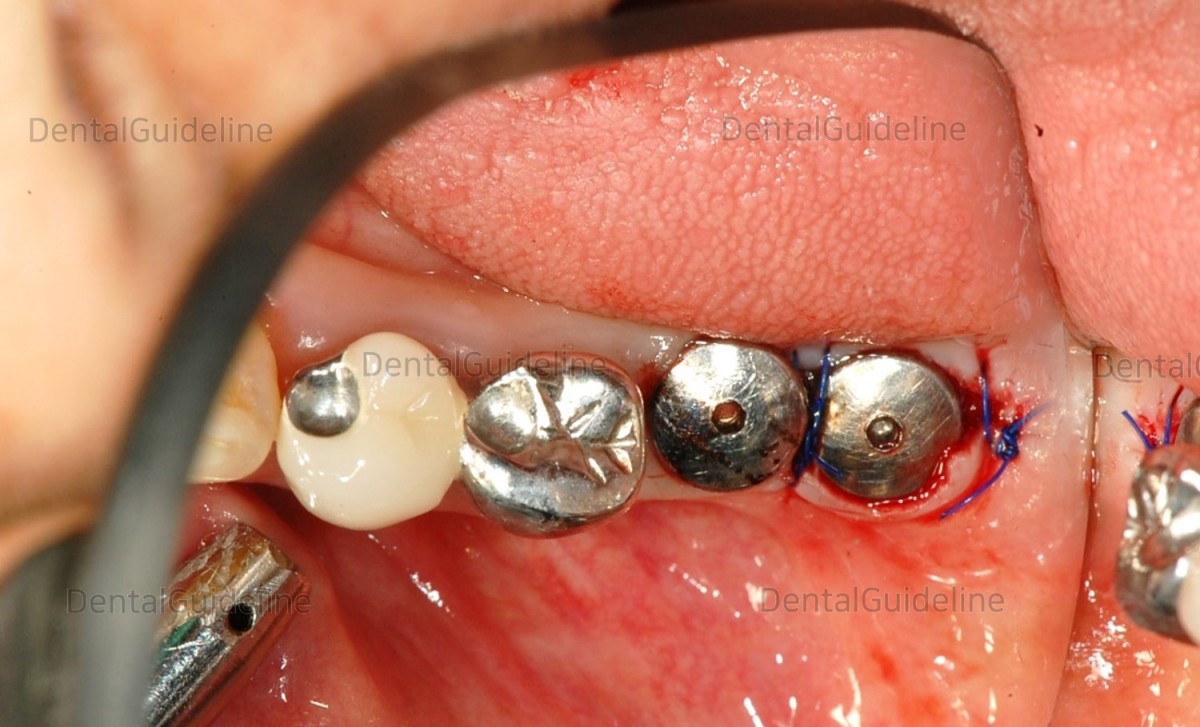

66-year-old female, Cleft

Lip & Palate, Osteoporosis ; stop taking BSP, 2months before surgery.

photo on the day of implant surgery.![]()

The

flap was opened and two implants were placed. Finally, it was decided on a

3-unit implant-supported fixed partial denture.![]()

suture.